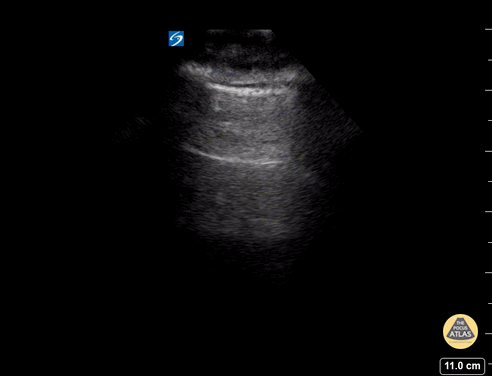

Pulmonary - A - Lines - Normal Lung

A lines appear as horizontal lines that represent normal aerated lung (dry interlobular septa). They are a reverberation artifact caused by the sound waves bouncing off the highly echogenic pleura and back to the probe, and repeating. Hannah Kopinski (MS4) and Dr. Lindsay Davis - NYU Emergency Medicine, Matthew Riscinti - Kings County Emergency Medicine